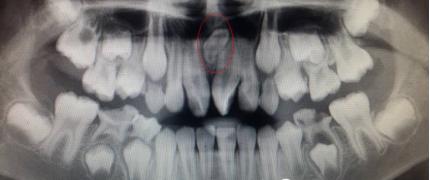

儿童口腔科的医生经过专科查体并配合X线检查,发现是孩子的两颗新长门牙之间有一颗多生牙在作怪,这让李奶奶更紧张了。

临床上发现或有多生牙时,需要拍摄X线片来明确诊断,如牙齿根尖片、全口曲面断层片或CBCT等,确定多生牙的数目和位置。为了减少多生牙对恒牙和恒牙列的影响,应尽早发现,及时处理。已经萌出的多生牙应及时拔除,以有利于邻近恒牙的顺利萌出并减少恒牙的错位。若萌出的多生牙形态与正常牙相似或牙根有足够的长度,而相邻的正常牙齿有牙根吸收、牙根弯曲等问题,可以综合考虑全牙列的情况后拔除相对较差的正常牙而保留多生牙。对于埋伏的多生牙,如果影响恒牙的发育、萌出及排列,在不损伤恒牙胚的情况下应尽早拔除,若不影响恒牙胚发育和萌出,则可等到恒牙牙根发育完成后再拔除。埋伏的多生牙拔除术后还要关注定期复查。